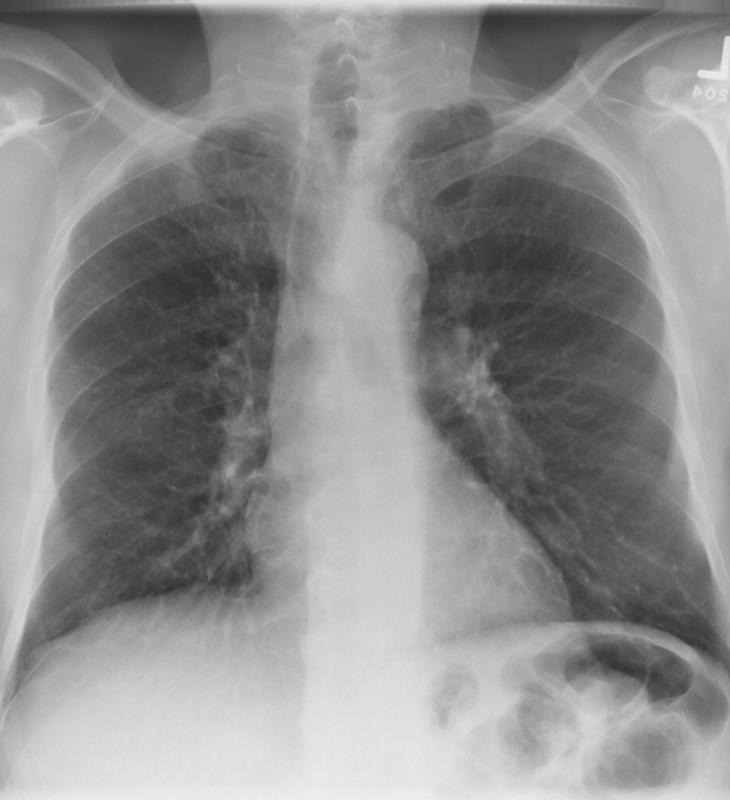

Gallery Lung Cancer Mets Prostate PA before

Prostate PA before